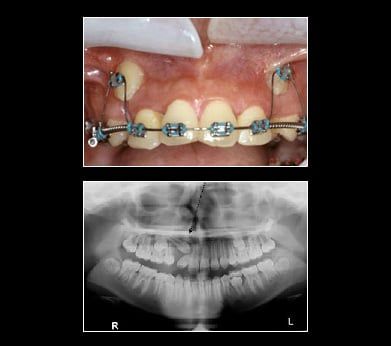

Impacted Canine

The fact that teeth don't always come in like they're supposed to highlights the need for regular dental visits when young teeth are developing. If you suspect your child has impacted canines, don't hesitate to make an appointment with Peak Periodontics & Implants. With regular dental visits, x-rays and examinations, the problem of impacted canines can be found out early when treatment is easier. If you are an adult and your canines have not erupted Peak Periodontics & Implants can help. Set an appointment today for an x-ray and consultation. Your smile is up there waiting for you.

Treatment for Impacted Canines

After assessing your situation, Peak Periodontics & Implants will devise a plan to make room for your canines.